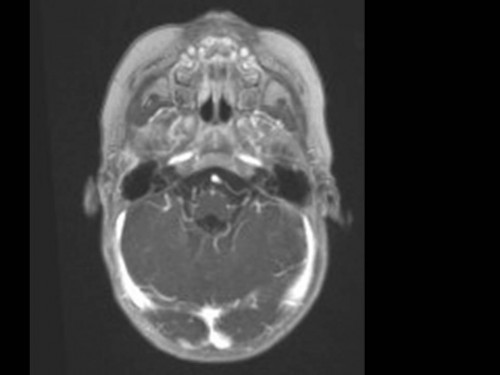

10 Monate altes Mädchen. Der Kinderarzt stellt fest, dass das kleine Mädchen einen recht großen Kopfumfang hat, nicht mit den Augen fixiert und anscheinend auch nicht richtig sehen kann. Damit bestätigt er die größten Befürchtungen der Eltern, denen in den letzten Wochen aufgefallen war, dass ihre Tochter nach keinem Spielzeug mehr greift und sie nur dann anlächelt, wenn sie zu ihr sprechen.

Bildgebung - MRT